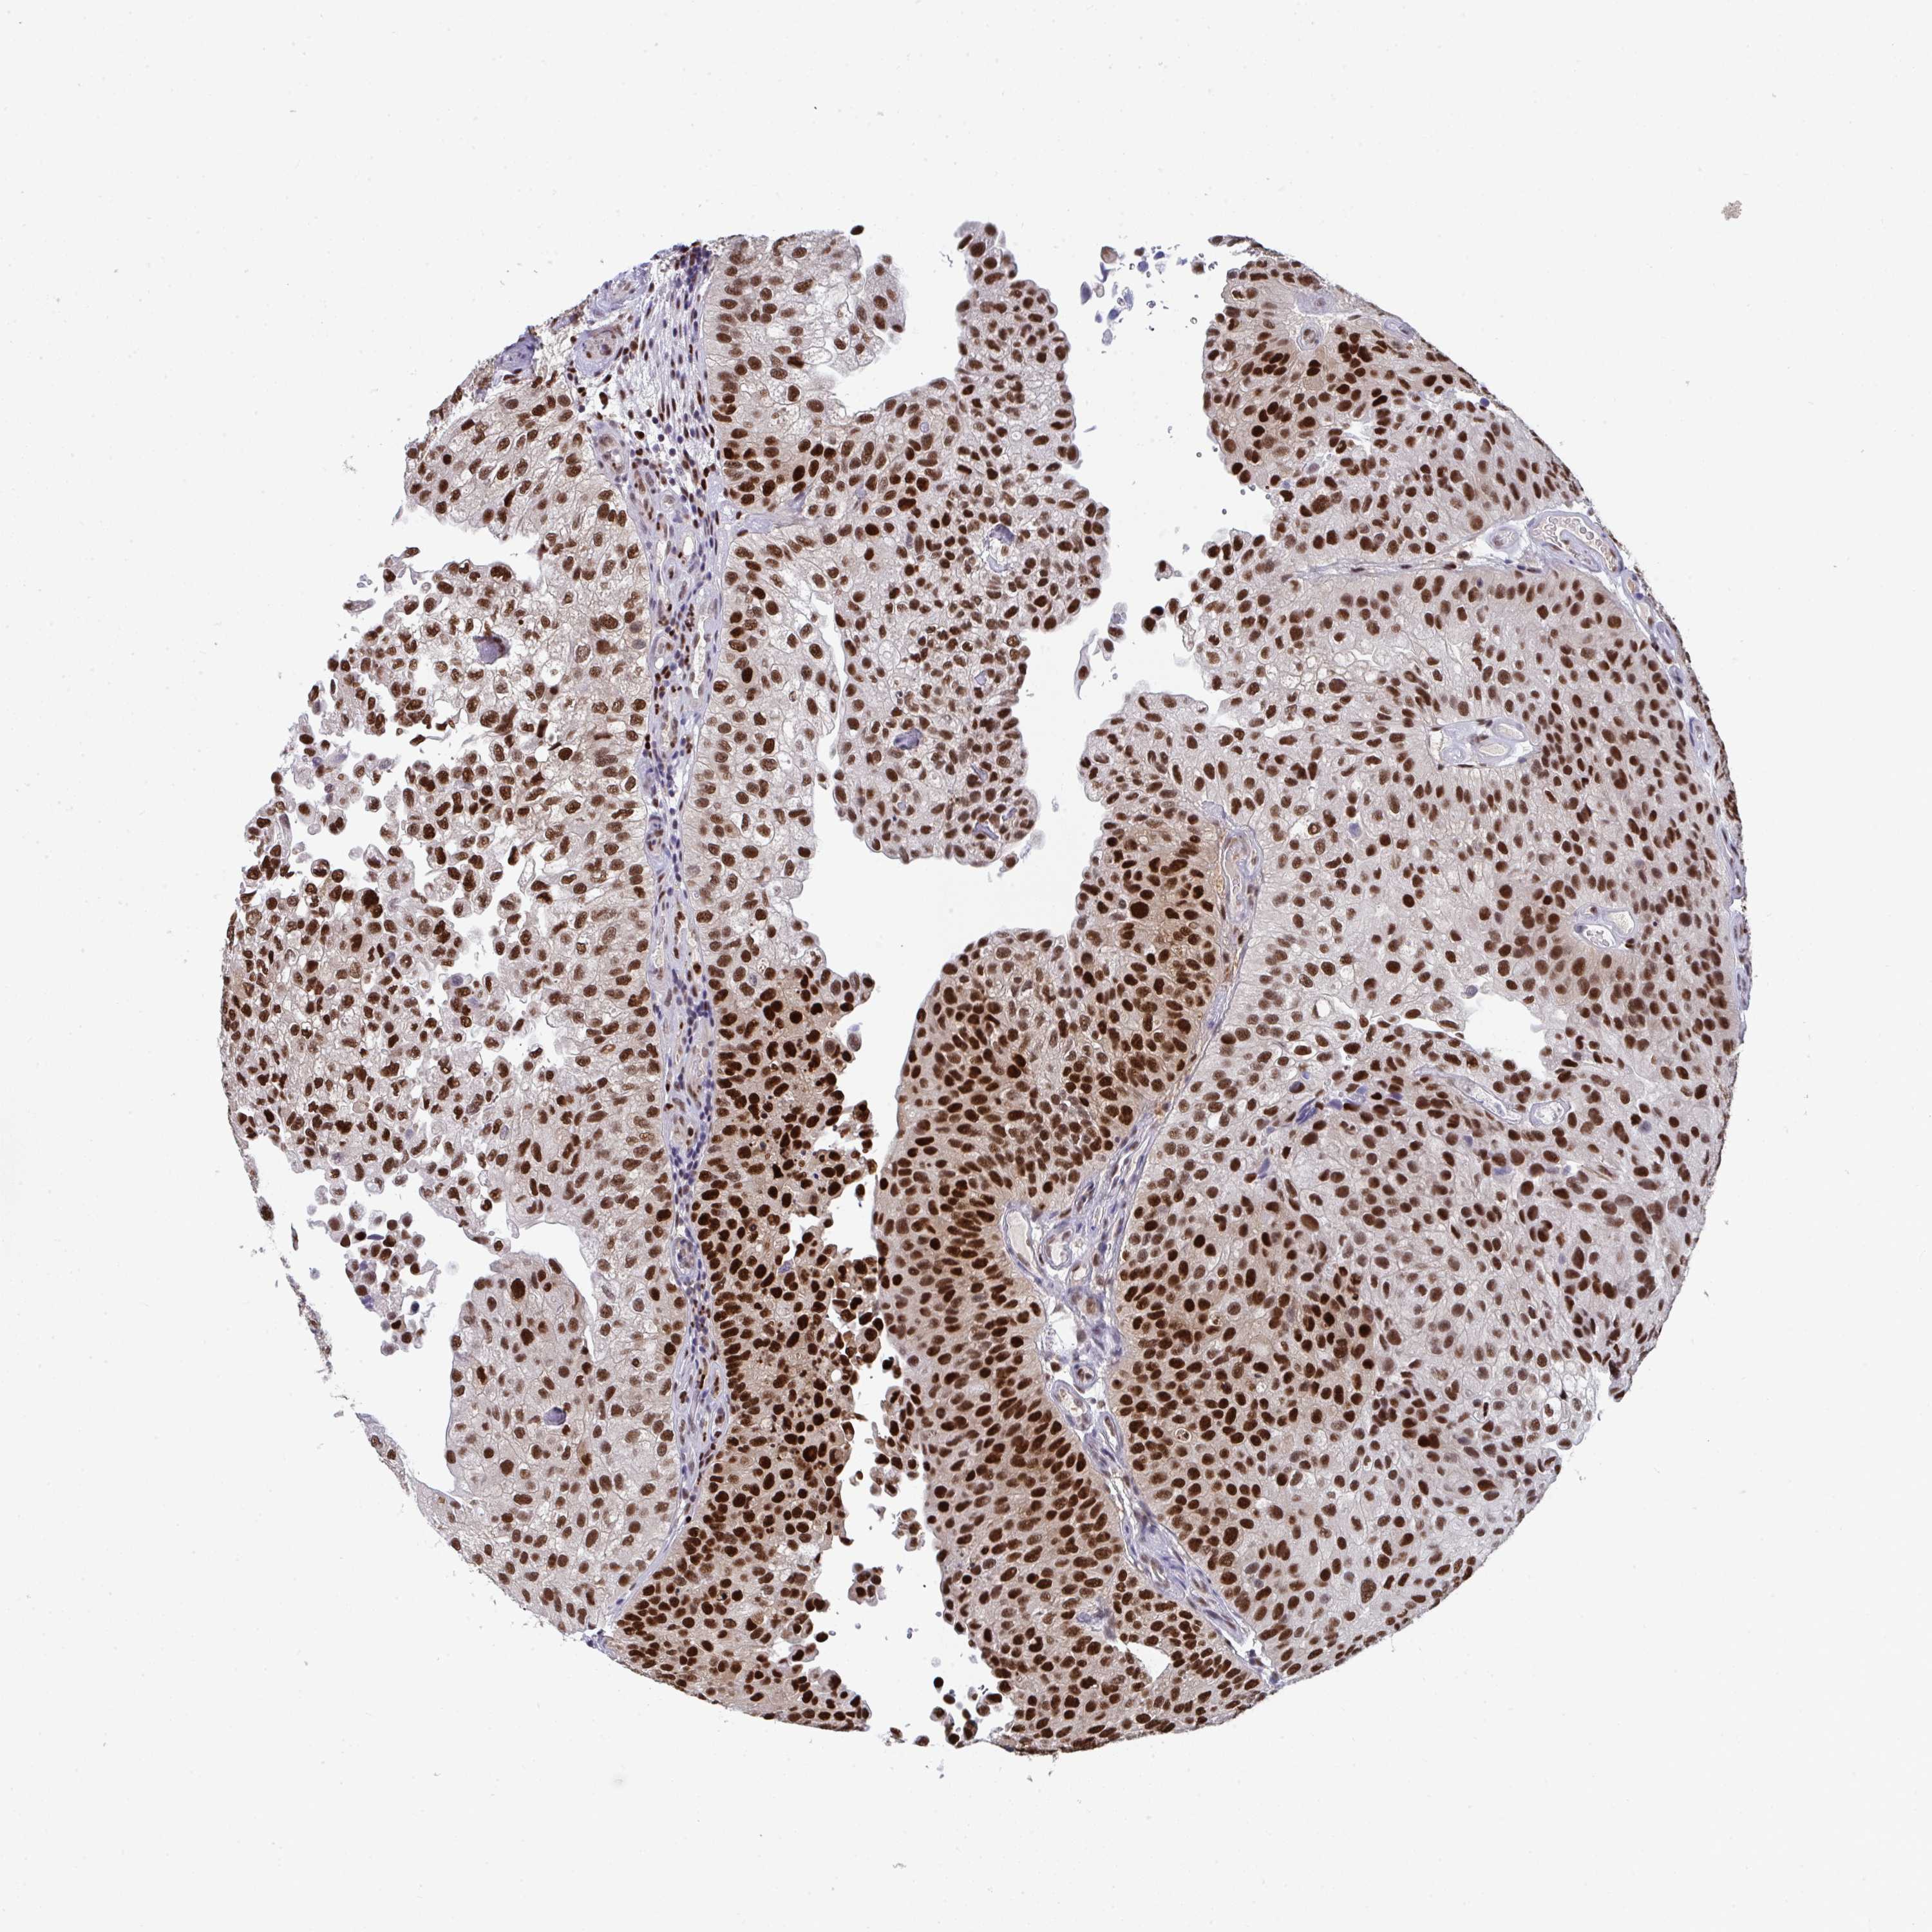

UROTHELIAL CANCER - Protein expressioni

A mouse-over function shows sample information and annotation data. Click on an image to view it in a full screen mode. Samples can be filtered based on level of antibody staining by selecting one or several of the following categories: high, medium, low and not detected. The assay and annotation is described here.

Antibody stainingi

Antibody staining in the annotated cell types in the current human tissue is reported as not detected, low, medium, or high, based on conventional immunohistochemistry profiling in selected tissues. This score is based on the combination of the staining intensity and fraction of stained cells.

Each image is clickable and will lead to virtual microscopy that enables deeper exploration of all samples and also displays staining intensity scores, fraction scores and subcellular localization as well as patient and tissue information for each sample.

Antibody HPA059511

Staining

High

Medium

Low

Not detected

Intensity

Strong

Moderate

Weak

Negative

Quantity

>75%

75%-25%

<25%

None

Location

Nuclear

Cytoplasmic/membranous

Cytoplasmic/membranous,nuclear

Urothelial carcinoma, High grade

Urothelial carcinoma, NOS

Urothelial carcinoma, Low grade